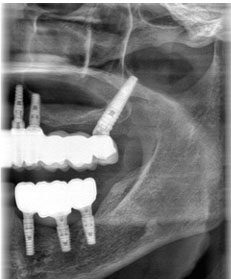

• Pianificazione Radiologica

• Fasi Chirurgiche del Posizionamento dell’impianto pterigoideo

• Panoramica del posizionamento

• Inserimento e angolazione

• Inserimento e posizione finale

• Radiografie e immagini di pazienti, video